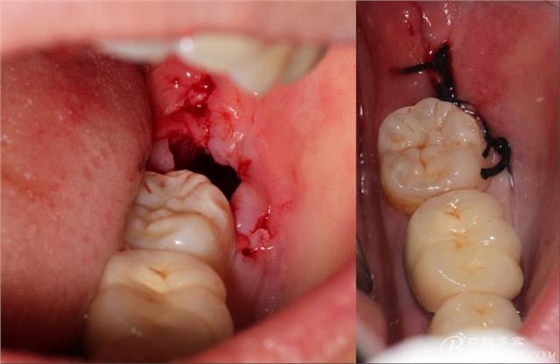

計劃總趕不上變化,何況是充滿變異的智齒。由于可操作空間較小,原來計劃橫向分根改成矢狀分根。

現(xiàn)在都在提倡微創(chuàng),個人看法微創(chuàng)是相對,所當然微創(chuàng)是我們的追求。完全撥出,縫合關閉創(chuàng)口,常規(guī)智齒撥除醫(yī)囑,不適隨診。